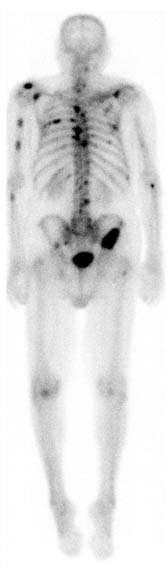

![]() A nuclear medicine whole-body bone scan. The nuclear medicine whole-body bone scan is generally used in evaluations of various bone-related pathology, such as for bone pain, stress fracture, nonmalignant bone lesions, bone infections, or the spread of cancer to the bone. | |